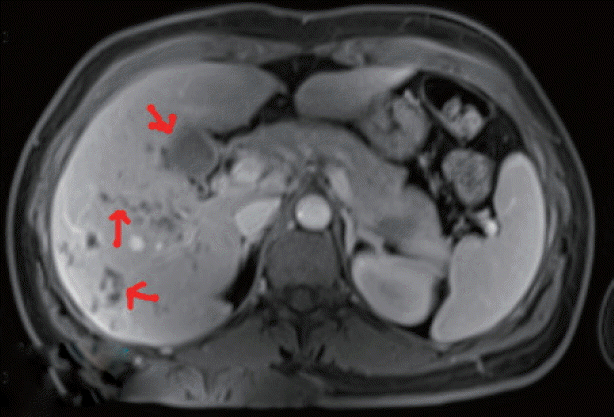

Based on routine, the doctors suspected a parasitic disease for the 4 patients, who were referred to Fujian Center for Control and Prevention. By stool sample analysis using water sedimentation method, Fasciola spp. eggs were found in Mrs. Xiao and her younger sister. Based on the shape and mean size (143×82 μm), the operculated eggs were identified as Fasciola spp. eggs (Fig. 3). Since the other 2 family members also consumed water dropwort and showed stomachache, all of them were referred to NIPD for further diagnosis.

Fig. 3

Operculated egg of Fasciola hepatica (143×82 μm) evidenced in stool samples by microscopy (×40).

Fig. 3 Operculated egg of Fasciola hepatica (143×82 μm) evidenced in stool samples by microscopy (×40).